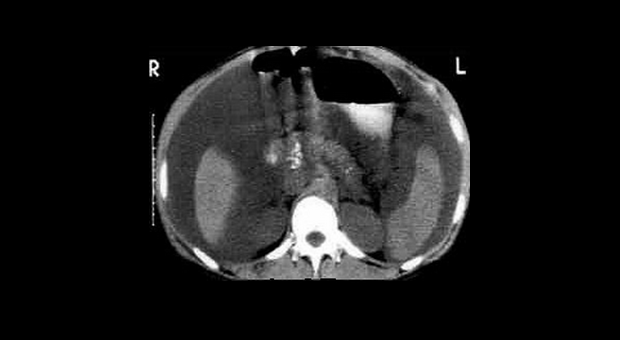

Иллюстрация №3: Компьютерная томография при хроническом панкреатите

Диагноз основывается на анамнезе и подтверждается визуализирующими исследованиями и лабораторными тестами, оценивающими структуру и функцию поджелудочной железы (рис. 2, 3) [9].

Амилаза и липаза сыворотки может соответствовать норме или быть незначительно повышена. У 5-10 % пациентов с хроническим панкреатитом компрессия дистальной части общего желчного протока ведет к увеличению билирубина сыворотки и щелочной фосфотазы. Мальабсорбция жира ведет к увеличению его экскреции с калом (более 7 грамм в день). Выявление панкреатических кальцификатов при рентгенографии, УЗИ или компьютерной томографии является диагностическим критерием хронического панкреатита. Эти кальцификаты обнаруживаются в примерно 25-60 % всех случаев хронического алкогольного панкреатита и у 35-80 % пациентов с панкреатитом другой этиологии. Компьютерная томография может также выявить локальное увеличение размеров поджелудочной железы, ее атрофию, расширение панкреатического протока или псевдокисту. РХПГ является наиболее чувствительным и специфическим визуализирующим исследованием в диагностике хронического панкреатита (рис. 3).